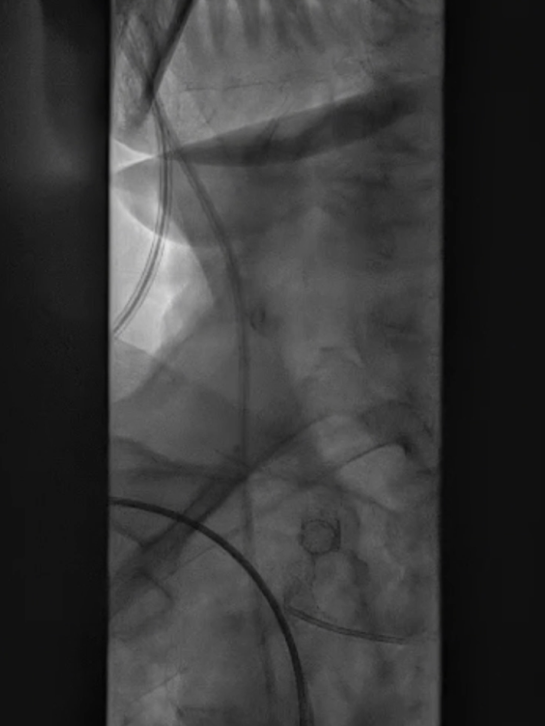

支架置入:通过“球囊带鞘”技术跟进长鞘至支架远端,采用同轴双导丝技术送入VBX8×29mm球扩覆膜支架,多角度造影定位后释放。

撤球囊时更进长鞘

至支架远端

同轴双导丝技术送入

VBX 8*29mm球扩覆膜

支架反复造影定位

释放支架